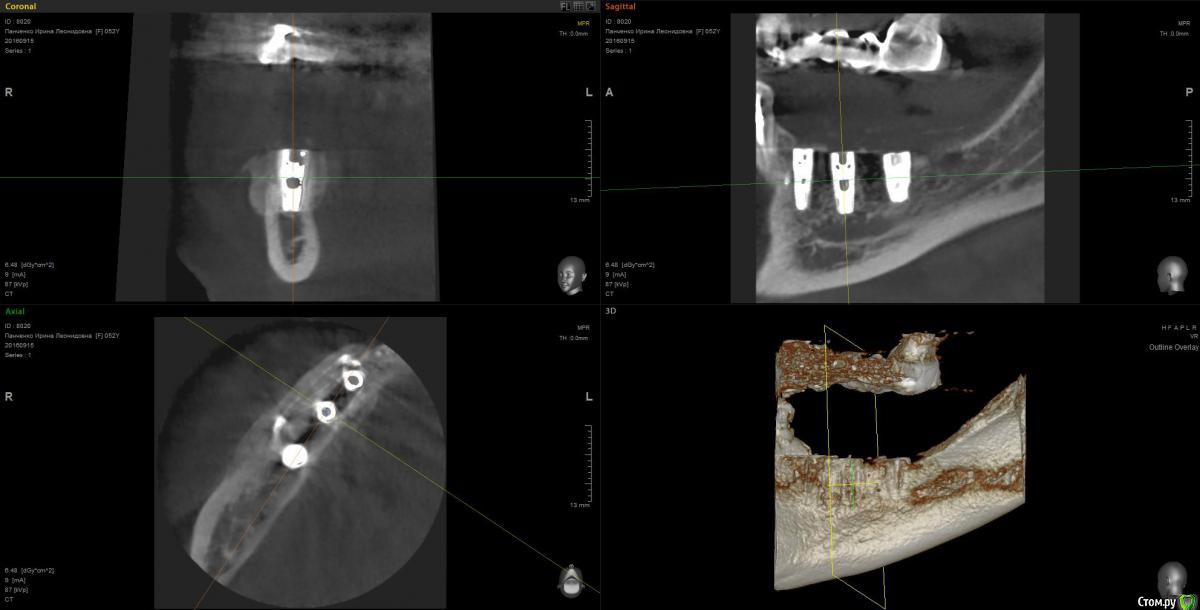

Kostoprav Опубликовано 13 марта, 2017 Поделиться Опубликовано 13 марта, 2017 рецепт сосиски: 70%биопласт by владмива +30%аутокость, мембрана hyprosorb кт до кт сразу после имплантации кт через пол года 3 Ссылка на комментарий

Kostoprav Опубликовано 14 марта, 2017 Автор Поделиться Опубликовано 14 марта, 2017 по порядку 8 Ссылка на комментарий

red_butler Опубликовано 26 марта, 2017 Поделиться Опубликовано 26 марта, 2017 Мембрану чем то фиксировали или уложили и ушили?посмотрите снимки еще раз, пины для мембраны на них видно Ссылка на комментарий